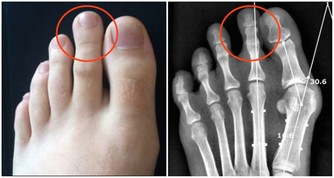

第三,注重足部的保健。糖友們每天自我檢查雙足,避免過度行走和勞累,選擇舒適的鞋襪。注意足部的清潔衛生和護理,洗腳的水溫不要超過40攝氏度,避免燙傷。